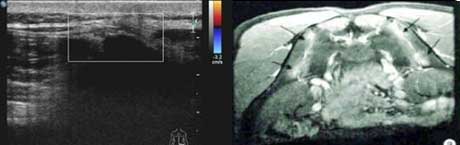

二、清晰显示滑膜炎性病变,提供早期骶髂关节病变线索

骶髂关节炎是强直性脊柱炎的显著特征,早期以滑膜炎性病变为主。肌骨超声对炎症血流十分敏感,可提示活动期强直性脊柱炎患者骶髂关节的异常血流增多变化,反映滑膜炎(滑膜增厚状况、滑膜形态表现、关节腔积液回声形态)表现,为活动性强直性脊柱炎早期骶髂关节病变提供重要线索。

滑膜状态

骶髂关节表面不同程度滑膜增厚、回声降低、关节间隙有明显强化灶。

血流信号

骶髂关节内部增厚的关节表面呈点状血流信号,可见多个小动脉点状血流信号。